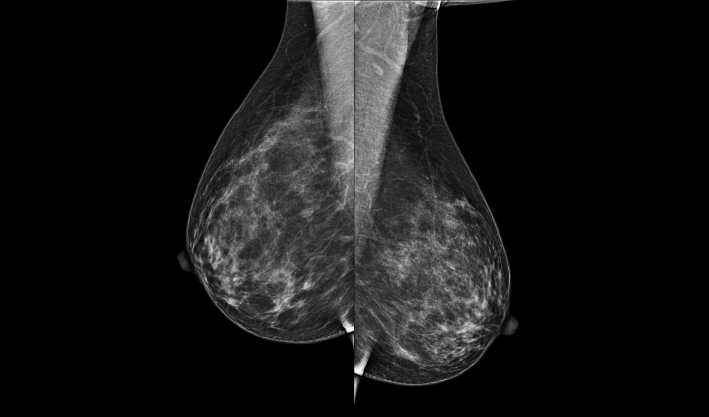

头尾位(CC位) 内外斜位(MLO位) 补充体位(根据需求)

一键式视图切换